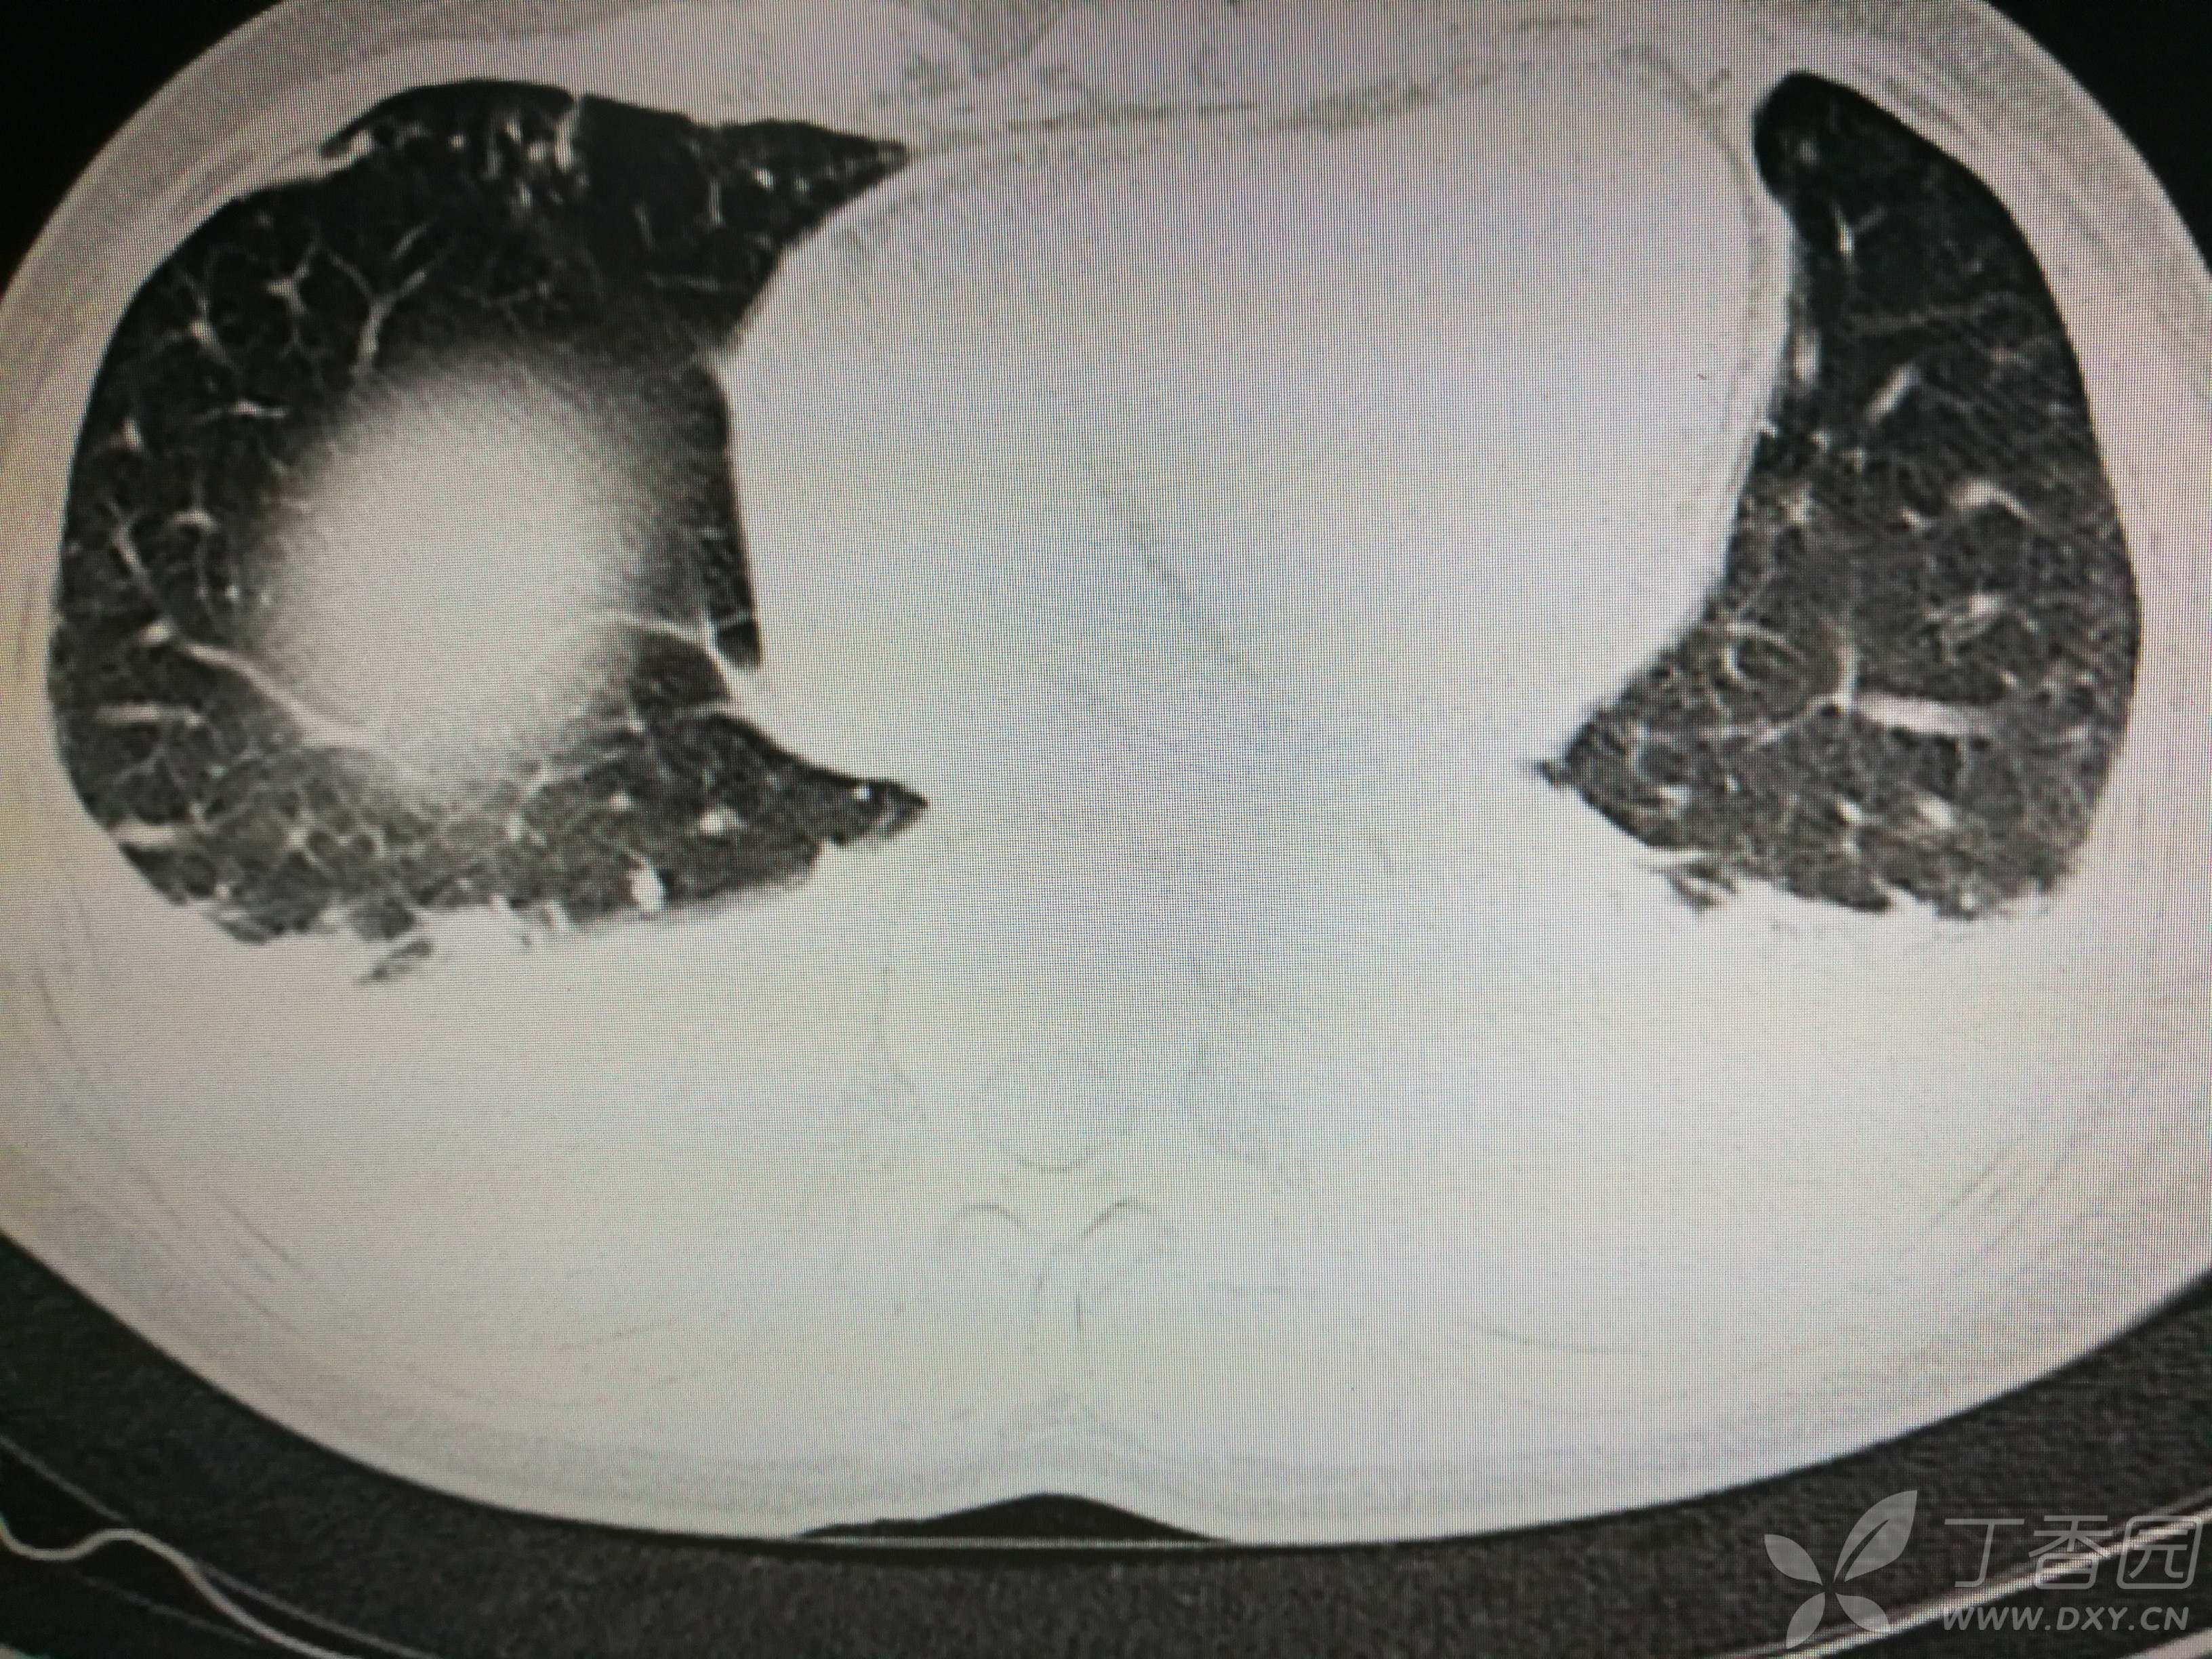

给予低分子肝素钙针抗凝、七叶皂苷钠针消肿及骨牵引固定等等治疗。入院后第四天行“左侧股骨下段骨折切开复位内固定术”(术前查双下肢彩超:双下肢深静脉血流通畅),手术顺利,术后予预防感染、预防血栓形成等治疗。术后患者无明显发热,生命体征平稳。术后第四天复查血常规:白细胞13.4×109/L,血红蛋白84g/L,血小板在正常范围。生化:白蛋白35.7g/L,余无明显异常。当天,患者开始出现轻度胸闷气急,可耐受。术后第五天患者胸闷气急加重,无胸痛,无背痛,无咯血,无意识障碍,无头晕头痛,无恶心呕吐等,急查凝血功能:纤维蛋白原降解产物12mg/L,D二聚体4000ug/L,余无明显异常。查动脉血气分析:pH7.52,氧分压62mmHg,二氧化碳分压30mmHg,碱剩余1.8mmol/L,乳酸1.0mm/L,血红蛋白86g/L。查胸部CT见下(先视频后图片):